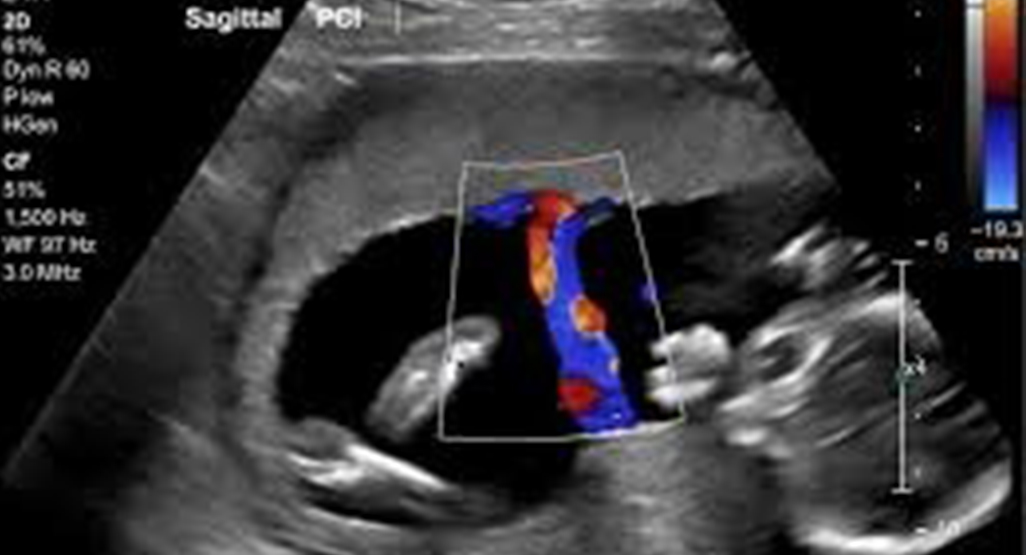

Checks blood flow in the carotid arteries. Helps assess risk of stroke or vascular blockages.

Assesses blood flow between mother, placenta, and baby. Ensures the fetus is receiving adequate oxygen and nutrition.